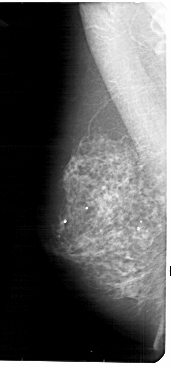

A_1831_1.LEFT_MLO

LEFT_MLO LINES 5491 PIXELS_PER_LINE 2551 BITS_PER_PIXEL 12 RESOLUTION 43.5 NON_OVERLAY